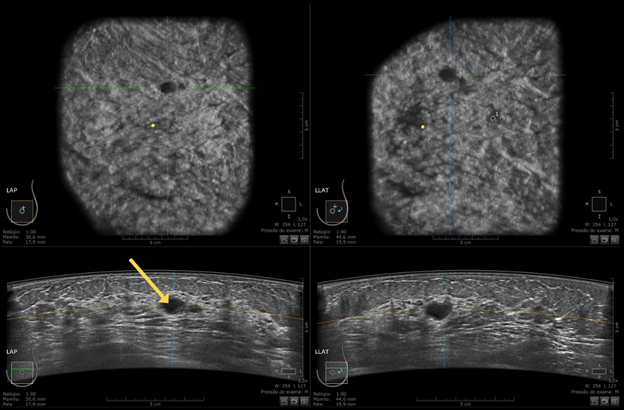

Tình trạng: Đánh giá nang vú dạng phức tạp.

Kết quả so sánh:

- HHUS (Hand-held Breast Ultrasound) – Siêu âm 2D truyền thống: Nghi ngờ nang phức tạp – Xếp loại BI-RADS 4 (Cần sinh thiết).

- ABUS: Xác định rõ mức dịch bên trong nang – Xếp loại BI-RADS 2 (Lành tính)

Hình 3. ABUS ghi nhận tổn thương dạng nang phức tạp, có mức dịch–dịch bên trong (mũi tên vàng), phù hợp phân loại BI-RADS 2

- Đối chiếu MRI: Đồng nhất với kết quả ABUS, không ngấm thuốc đối quang từ – Xếp loại BI-RADS 2